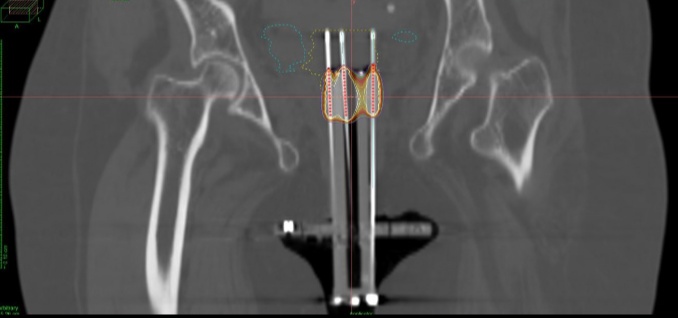

फरीदाबाद के अमृता हॉस्पिटल रेडिएशन ऑन्कोलॉजी विभाग में प्रोफेसर और एचओडी डॉ. भास्कर विश्वनाथन ने कहा, “महिला का इलाज पहले केमोरेडिएशन और एक्सटर्नल बीम रेडिएशन से किया गया था जो आमतौर पर सभी जगह की जाती है। पहले हुए इलाज की वजह से उसके गर्भाशय और पैरामीट्रिया के फाइब्रोसिस के कारण, उसके मामले में एक विशेष इलाज की आवश्यकता थी। बार-बार होने वाले सर्वाइकल कैंसर और पूर्व उपचारों से जटिलताओं का सामना करते हुए, रोगी को तत्काल थैरेपी की आवश्यकता थी। सर्वाइकल ट्रांसरेक्टल-गाइडेड इंटरस्टिशियल ब्रैकीथेरेपी एक विशेष और अभिनव दृष्टिकोण है, जो स्वस्थ टिश्यू को बचाते हुए टार्गेटिड, हाई-डोज़ वाली रेडिएशन को सीधे ट्यूमर तक पहुंचाता है। MUPIT एप्लिकेटर, प्री-ब्रैकीथेरेपी एमआरआई और रीयल-टाइम गाइडेंस का उपयोग करते हुए, इस तकनीक ने दुष्प्रभावों को कम करने में अपनी क्षमता का प्रदर्शन किया। रोगी के रेडिएशन इलाज के इतिहास को ध्यान में रखते हुए, आसपास के अंगों को संरक्षित करते हुए कैंसर को एक प्रभावी खुराक प्रदान करने का नाजुक संतुलन हासिल किया गया। पूरी प्रक्रिया एनेस्थीसिया के साथ 1 घंटे तक चली।

इसकी प्रभावशीलता के बावजूद, सर्वाइकल ट्रांसरेक्टल-गाइडेड इंटरस्टिशियल ब्रैकीथेरेपी आमतौर पर भारत में नहीं की जाती है, जो इस प्रक्रिया को विशेष रूप से उल्लेखनीय बनाती है। यह एक विशेष तकनीक है जो गर्भाशय ग्रीवा और पैरामीट्रियम में ट्यूमर के दृश्य के लिए रेक्टल अल्ट्रासाउंड का उपयोग करती है। इस प्रक्रिया में मूत्राशय, मलाशय और आंत्र जैसी महत्वपूर्ण संरचनाओं पर अनावश्यक जोखिम को कम करते हुए ट्यूमर तक रेडिएशन की टार्गेटिड डिलीवरी सुनिश्चित करने के लिए ब्रैकीथेरेपी में सुइयों की सटीक नियुक्ति शामिल है। इसका उद्देश्य आसपास के सामान्य टिश्यू की सुरक्षा करते हुए ट्यूमर क्षेत्रों में खुराक को अनुकूलित करना है। प्रक्रिया की दुर्लभता, फ़ाइब्रोस्ड पैरामीट्रिया द्वारा उत्पन्न चुनौती के साथ मिलकर, एक नाजुक संतुलन बनाया गया जिसे बनाने की आवश्यकता थी। इन चुनौतियों के बावजूद, अमृता अस्पताल, फरीदाबाद में डॉक्टरों की एक टीम, जिसमें डॉ. भास्कर विश्वनाथन, रेडिएशन ऑन्कोलॉजी के असिस्टेंट प्रोफेसर डॉ. ऋषभ कुमार और रेडिएशन ऑन्कोलॉजी की सीनियर कंसलटेंट डॉ. निवेदिता सरकार शामिल थीं, ने कम रक्तस्राव और बिना किसी समस्या के प्रक्रिया को सफलतापूर्वक पूरा किया।